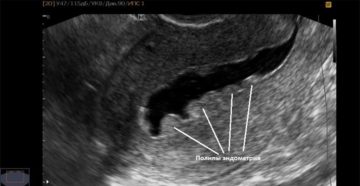

Узи диагностика при выявлении полип эндометрия Широкое внедрение методов ультразвуковой диагностики позволяет обнаружить патологию на…